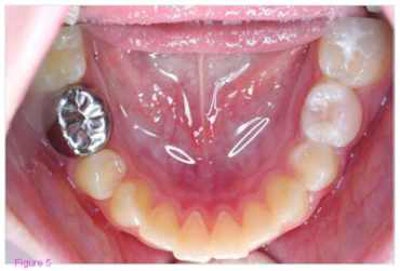

The study examined the Hall technique, in which dentists do not prepare the surface of the tooth they are treating or use anesthesia. Instead, they simply cement a preformed metal crown over the surface, sealing the cavity underneath.

To test the technique, investigators from Dundee Dental Hospital and School in Dundee, Scotland, compared 128 primary molars treated with conventional restorations to 128 primary molars treated with the Hall technique. For the conventional restorations, dentists drilled out lesions and restored cavities with glass ionomer cement, amalgam, compomer, composite, a preformed molar crown, or a fissure sealant. Four teeth got no restoration. Each Hall technique treatment was paired with a conventional one in the same mouth.

Though the crowns increased the heights of the treated teeth by about 2.5 mm, all the patients maintained full occlusal contact after treatment.